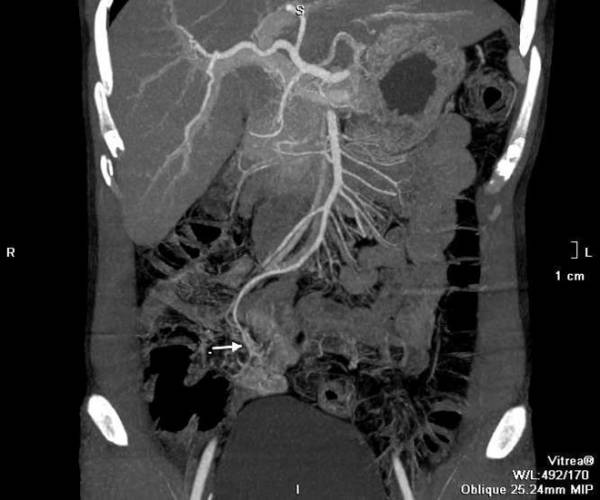

Sau hồi sức tích cực, anh C. được tiến hành chụp CT. Các bác sĩ phát hiện búi dị dạng mạch máu từ một nhánh của động mạch mạc treo tràng trên, nằm ngay trên thành ruột non, đang có dấu hiệu chảy máu. Đây là thủ phạm gây chảy máu kéo dài.

Bệnh nhân được hội chẩn, điều trị khẩn cấp bằng phương pháp can thiệp mạch để nút búi dị dạng. Trong quá trình tiến hành thủ thuật, bác sĩ can thiệp luồn một ống thông nhỏ đường kính chỉ khoảng 1 mm từ động mạch đùi tại vùng bẹn, qua động mạch chủ bụng vào động mạch mạc treo tràng trên, dưới hướng dẫn của máy X-quang số xóa nền.

Tiếp theo bác sĩ can thiệp luồn một ống thông nhỏ hơn vào lòng ống thông đầu tiên và đưa đầu vi ống thông đến tận mạch máu dị dạng. Sau khi bơm thuốc cản quang xác định chính xác đầu vi ống thông đến ổ dị dạng, bác sĩ can thiệp bơm các hạt nút mạch để nút toàn bộ các mạch máu dị dạng. Sau thủ thuật 24 giờ, bệnh nhân không còn triệu chứng chảy máu, sức khỏe phục hồi.